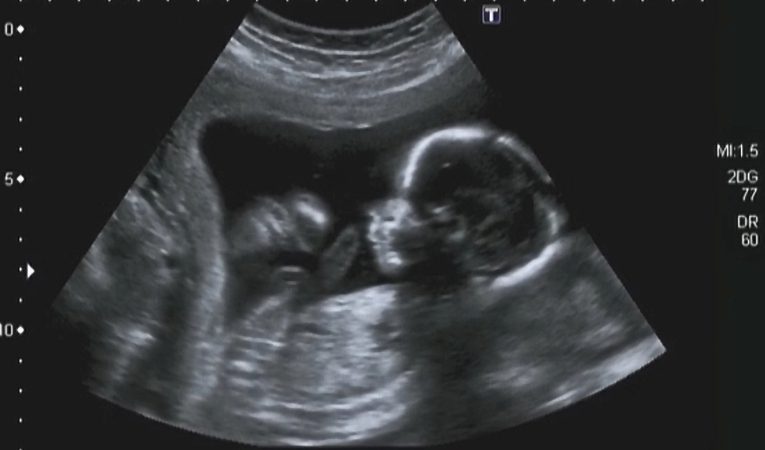

AKRANIJA je poremećaj u razvoju kostiju glave u fetusa. Poremećaj u razvoju plosnatih kostiju lubanje (neurokranija) – odsustvo svoda lubanje. Kosti neurokranija, odnosno plosnate kosti lubanje počinju sa osifikacijom (okoštavanjem) već potkraj prvog tromjesečja, tako da tada postaju vidljive, odnosno dostupne ultrazvučnoj dijagnostici. Ako se u tom gestacijskom dobu ultrazvukom ne vidi okoštala lubanja, postavlja se sumnja na akraniju. Nedostatak svih kostiju neurokranija (akranija), može biti udružen i sa nedostatkom mozga (anencefalija), moždano tkivo može biti prepoznato kao nepravilna i neorganizirana masa koja se sastoji od moždanog tkiva, moždanih ovojnica i krvnih žila. Takva masa bez kostiju svoda lubanje slobodno pluta u plodovoj vodi neposredno iznad baze lubanje (egzencefalija). Kod izolirane akranije rijetki su kromosmski poremćaji u fetusa. Akranija može biti udružena sa ostalim malformacijama središnjeg živčanog sustava fetusa.

EGZENCEFALIJA – prisutno je deformirano moždano tkivo, deformirane hemisfere mozga i deformiran mali mozak, moždano tkivo je prekriveno nježnim moždanim ovojnicama. Odsustvo svoda lubanje iznad orbita, prisutna je baza lubanje i normalno lice.